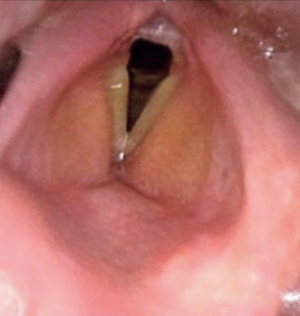

血液所見:赤血球 456万、Hb 11.9 g/dL、Ht 36 %、白血球 14,900(好中球 88 %、リンパ球 7 %、単球 5%)、血小板 23 万。血液生化学所見:総蛋白 7.3 g/dL、アルブミン 3.5 g/dL、AST 10 U/L、ALT 8 U/L、 尿素窒素 21 mg/dL、クレアチニン 0.9 mg/dL、Na 135 mEq/L、K 4.2 mEq/L、Cl 98 mEq/L、Ca 9.6 mg/dL。CRP 29 mg/dL。咽頭と喉頭の内視鏡像、頭頸部造影 CT 水平断像及び冠状断像を別に示す。

治療として適切なのはどれか。2 つ選べ。